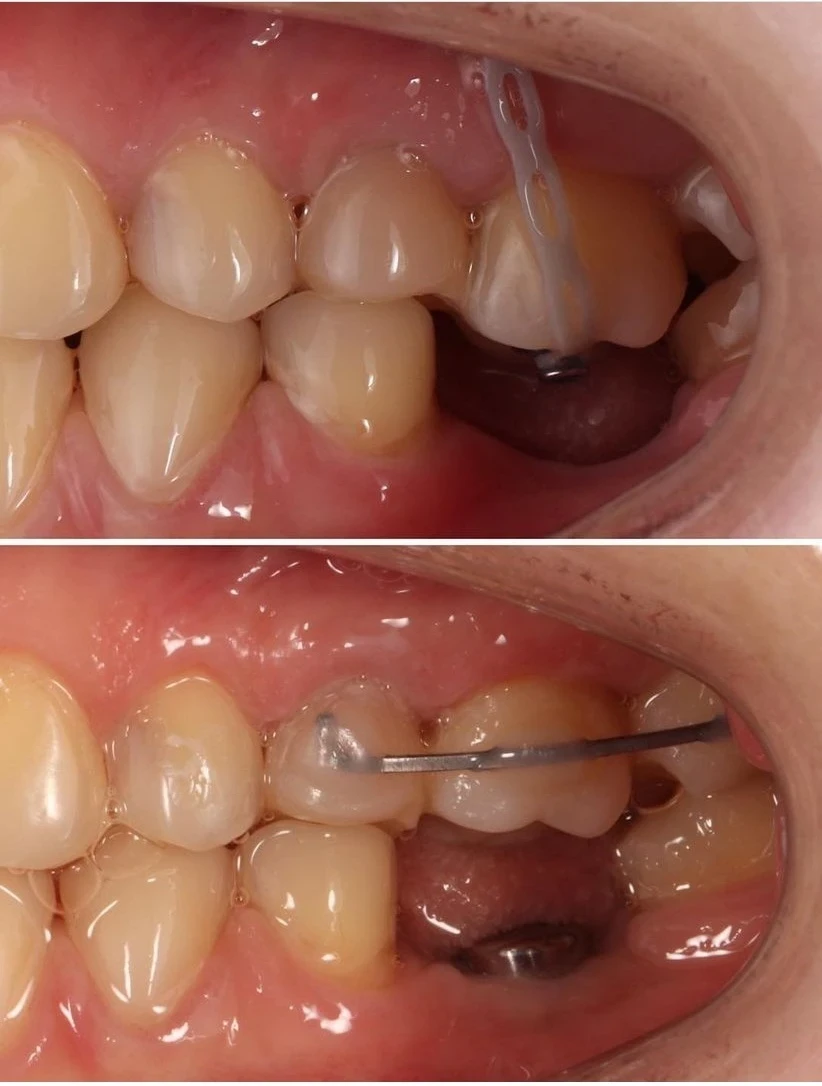

L'orthodontie pré-prothétique

Pourquoi ne pas envisager l’orthodontie préprothétique, dans certains cas, avant de recourir aux autres types de traitements orthodontiques ?

Les reconstructions prothétiques ou implantaires obéissent à certains critères : espace suffisant pour les dents artificielles, parallélisme relatif des racines dentaires, répartition satisfaisante des espaces, absence d’égression de dents antagonistes vers les sites édentés, occlusion correcte, etc.

Si ces critères ne sont pas réunis, le projet prothétique ne pourra palier les défauts que jusqu’à un certain point. La restauration prothétique pourrait même s’avérer impossible ou nécessiter une taille des dents plus importante que prévue.

Ainsi, lorsque certaines anomalies d’occlusion induisent le risque de complexifier la réalisation prothétique, voire de la rendre impossible, la première phase de traitement orthodontique pré-prothétique aura pour objectif de faciliter la phase prothétique ou de la rendre réalisable.

Les objectifs :

Faciliter ou permettre la réalisation de la prothèse en redressant l’axe de la molaire mésioversée, par la correction d’une égression iatrogène (dent qui monte, ou qui descend selon la localisation).

Répartir correctement les espaces entre les dents.

Éviter la prothèse, notamment après l’extraction d’une dent, en refermant l’espace créé par le déplacement orthodontique.